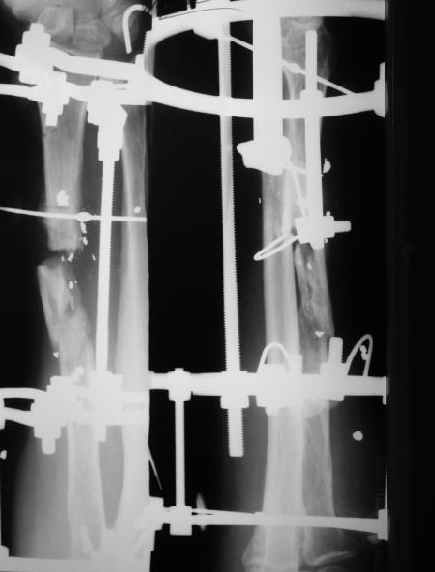

Re: Огнестрельный перелом луча

В приложении - снимок по окончании дистракции, и после смены аппарата на стержень (довольно толстый, 5 мм). С входом в канал на центральном отломке пришлось малость попотеть, промежуточный отломок его прикрывал. Но все-таки удалось закрыто проколупать. Надеюсь, дня через 3-4 после операции можно будет передать пациента нейрохирургам. Буду признателен за критику и комментарии.